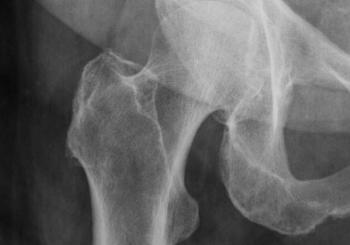

Patients taking nitrogen-containing bisphosphonates have a lower risk of developing and dying from pneumonia after hip fracture compared with patients taking other types of medication for osteoporosis or no drugs for osteoporosis at all, a study published in the Journal of Bone and Mineral Research has found.